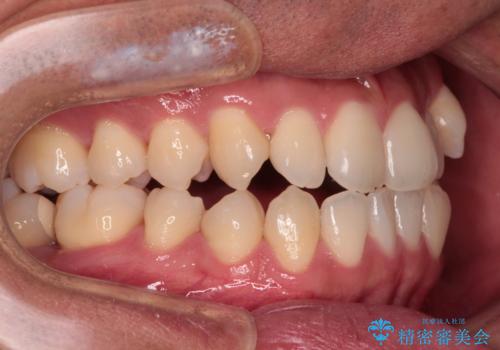

- 上下前歯部のデコボコを主訴として来院された患者様です。

上顎の歯列弓が下顎に対して狭いため、臼歯のかみ合わせがが咬頭対咬頭の状態です。